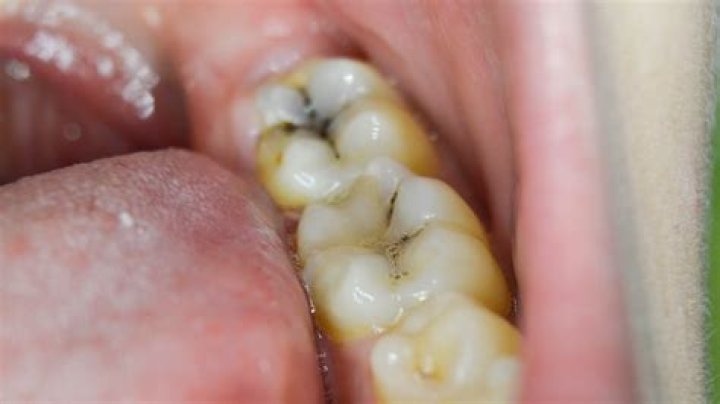

Often a cavity will look like a dark spot on the tooth, typically yellow, brown, or black in color. Early on, it may resemble tooth staining or a slight discoloration. As cavities progress, the holes get bigger and usually darker.

Cavities vary greatly in appearance. In general, however, they appear as small holes, chips or dark spots on teeth. The holes can be as small as dots or as large as the entire tooth. Sometimes they look brown, yellow or black.

What does early stage cavity look like?

Does a black spot on tooth mean cavity?